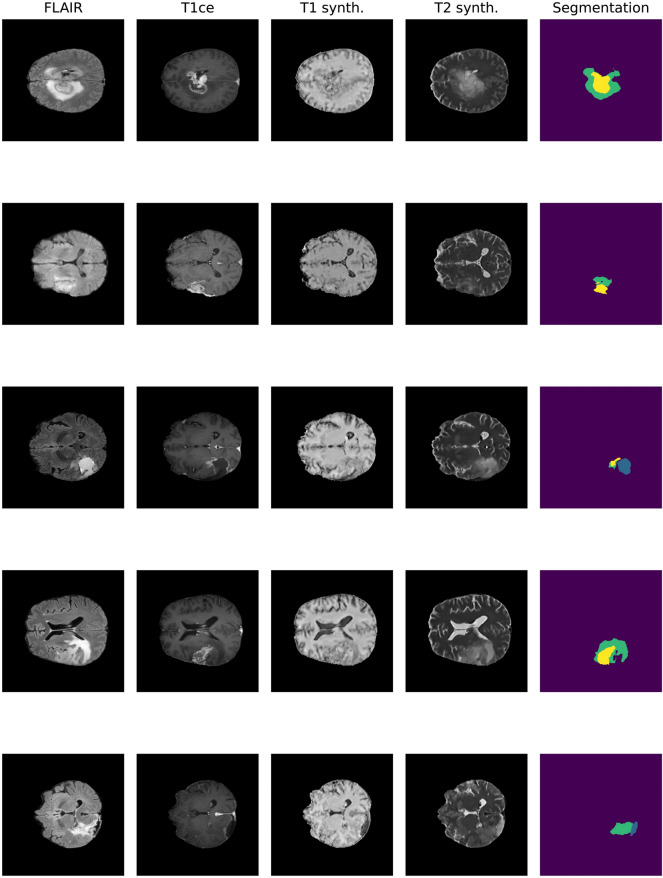

Fig. 2.

Application of the IMT U-Net architecture to postoperative MRI from the Molinette Hospital dataset. The different rows refer to representative slices from five randomly extracted patients (blue: cavity, yellow: enhancing, green: whole)

In this work, this last proposal was chosen: a 2D U-Net, receiving as input single MRI slices, was built in order to learn from the BraTS dataset the non-linear mapping between available and desired sequences.

These artificial sequences, although in a way “hallucinated” by the network, could be used in place of missing sequences, thus allowing the network to be trained on studies with a variable number of sequences. In this study, both strategies were compared. The modified U-Net structure originally proposed by Osman and Tamam [26] was implemented to artificially synthesize the missing sequences, stacking T1ce and FLAIR, hence exploiting information from both of them, instead of simply using a single sequence as input. The network was trained for 50 epochs with mixed precision on the BraTS 2021 dataset. The underlying U-Net required 2D inputs, therefore for each iteration a 3D scan was selected and a random selection of 64 2D slices (being this a reasonable amount of slices to balance computational cost and learning performances), possibly flipped along the two dimensions, was extracted and fed as a batch. The network was trained with the default Adam optimizer with a learning rate of 0.0003, which decays following a cosine schedule. Output images were shaped 224 × 224 so post-processing was applied to resize, re-orient and pad them in their BraTS form. Gaussian sharpening was also applied as further data augmentation. The synthesis was carried out using the T1ce MRI acquisition, as the additional use of non-volumetric FLAIR scans would eventually generate noisy outputs.